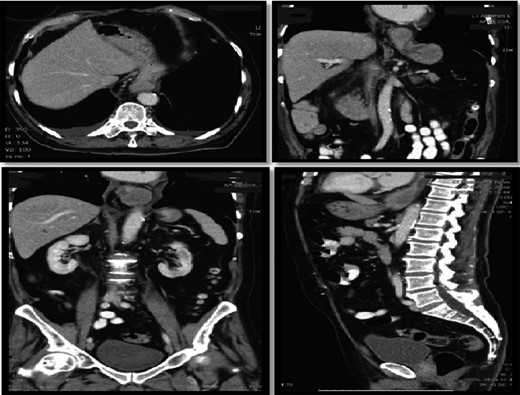

On assessment, he was hypertensive, normal heart rate and temperatures. Abdominal exam was unremarkable. Laboratory tests were all within normal range. CT Abdomen showed distal esophageal mural thickening suggestive of esophagitis in small hiatus hernia with bilateral pleural effusions (Fig. 5).